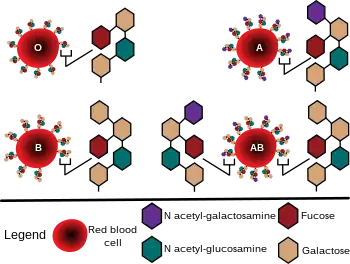

The first practical use of blood typing in transfusion was by an American physician Reuben Ottenberg in 1907. Large-scale application began during the First World War (1914–1915) when citric acid began to be used for blood clot prevention.[10] Felix Bernstein demonstrated the correct blood group inheritance pattern of multiple alleles at one locus in 1924.[20] Watkins and Morgan, in England, discovered that the ABO epitopes were conferred by sugars, to be specific, N-acetylgalactosamine for the A-type and galactose for the B-type.[21][22][23] After much published literature claiming that the ABH substances were all attached to glycosphingolipids, Finne et al. (1978) found that the human erythrocyte glycoproteins contain polylactosamine chains[24] that contains ABH substances attached and represent the majority of the antigens.[25][26][27] The main glycoproteins carrying the ABH antigens were identified to be the Band 3 and Band 4.5 proteins and glycophorin.[28] Later, Yamamoto's group showed the precise glycosyl transferase set that confers the A, B and O epitopes.[29]

Diagram showing the carbohydrate chains that determine the ABO blood group

Student blood test. Three drops of blood are mixed with anti-B (left) and anti-A (right) serum. Agglutination with anti-A suggests this individual is type A. There are three basic variants of immunoglobulin antigens in humans that share a very similar chemical structure but are distinctly different. Red circles show where there are differences in chemical structure in the antigen-binding site (sometimes called the antibody-combining site) of human immunoglobulin. Notice the O-type antigen does not have a binding site.[30]